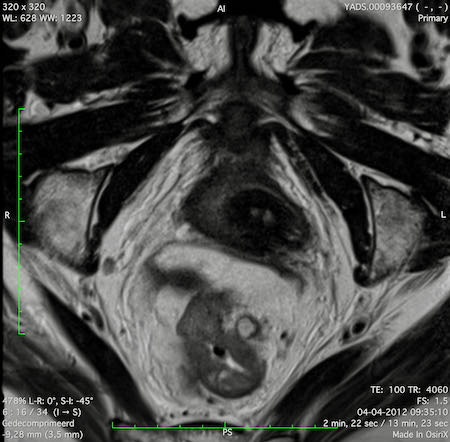

Hình ảnh

Các hình ảnh được cung cấp cho thấy ung thư biểu mô tế bào nhẫn với tình trạng dày lan tỏa thành trực tràng, hình ảnh bia bắn điển hình, và sự xâm lấn mỡ mạc treo trực tràng.